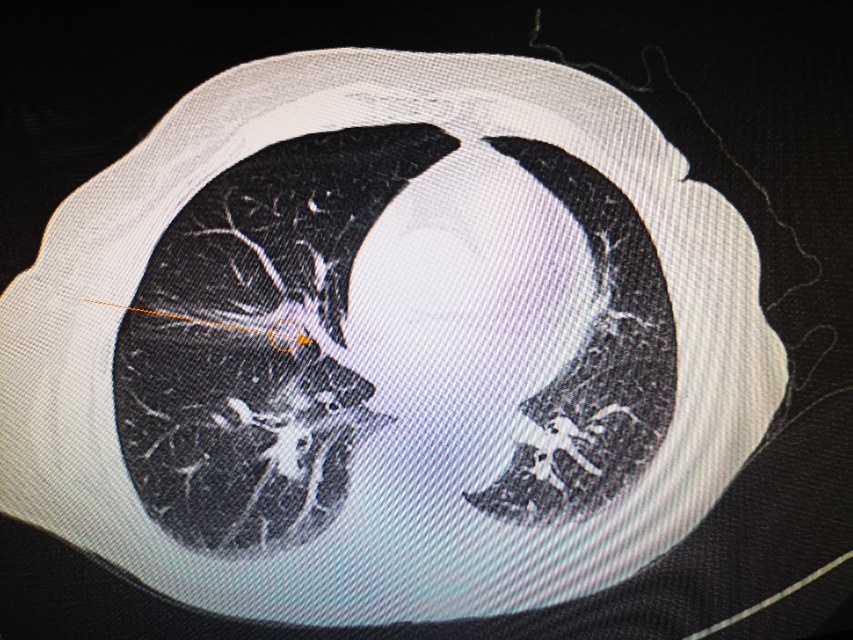

在穿刺针进入皮肤的那一刻,李医生就有感觉,今天的针应该是很准的。为了避开血管和胸膜,李医生中途停下两次,调整消融针的方向和角度,确保不损伤任何一根微小的血管,确保不影响任何一寸薄弱的胸膜!这个过程比穿的准要和更难更复杂!在团队的集体努力下,小李飞针终于避开所有血管、支气管和胸膜,到达了肺结节的中心!李医生的几位助手都长舒一口气。此时,我们回头看看钟奶奶,发现她安静的闭着眼睛,好像睡着了。就是现在,开始消融,经过仔细调整消融参数后,手术顺利取得了预期的效果。也没有气胸咯血等并发症。密室消磨,完美成功!